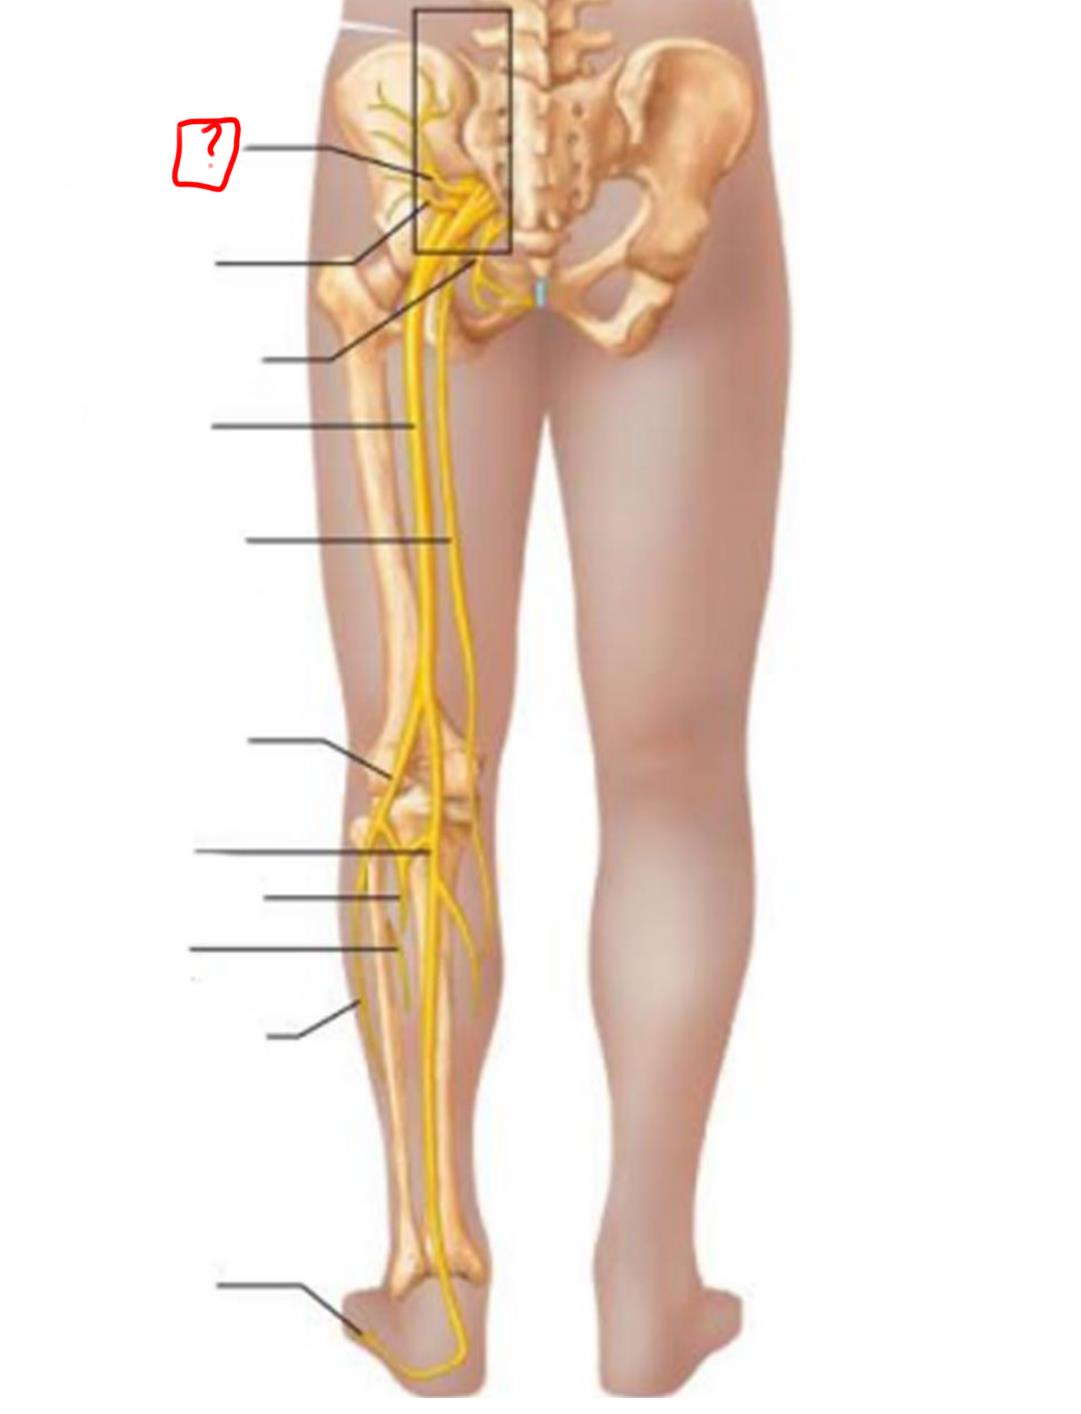

superior gluteal

inferior gluteal

pudendal

sciatic

posterior femoral cutaneous

common fibular

tibial nerve

sural (cut)

deep fibular

superficial fibular

plantar branches

superior gluteal

lumbosacral trunk

inferior gluteal

common fibular

tibial

posterior femoral cutaneous